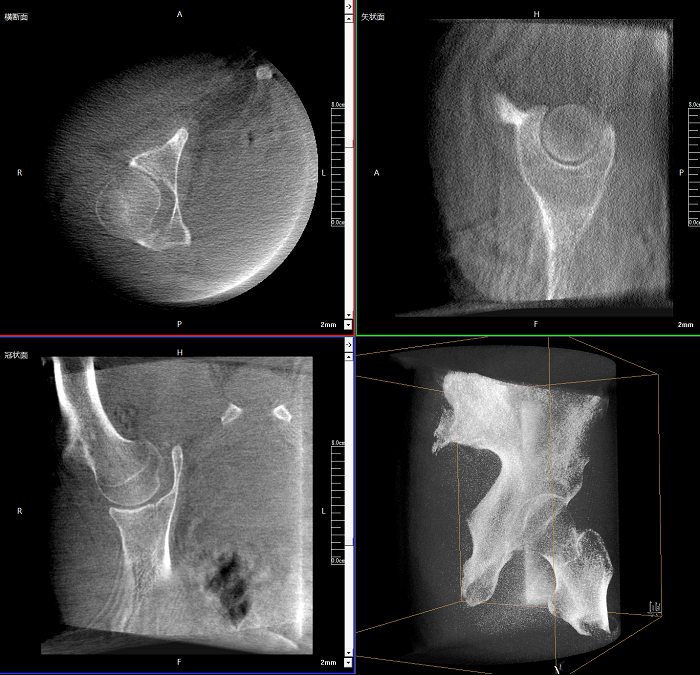

三维成像 全面观察

任意视角、任意切面观察

术中实时生成横断面、矢状面、冠状面及三维影像,可在任意切面、任意角度评估植入物和解剖结构的相对位置。

术中CT检查 减少翻修概率

通过术中三维影像的检查,可以立即发现植入物的错位,减少不必要的第二次手术,减少并发症概率以及感染风险。

Clinical picture

临床图片